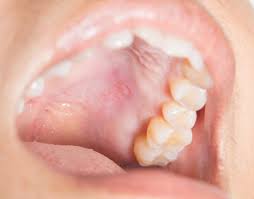

Allergic Reaction Bumps On Roof Of Mouth. STDs like Herpes and HIV infection. A bump on roof of mouth or palate can either be cancerous or non-cancerous. It could be allergies. If it is many bumps then it is an allergic reaction.

In this case lichen planus produces a similar small itchy bump on the roof of mouth which is also confused with an allergic reaction bump. Oral symptoms such as itching and tingling in the mouth and throat and slight swelling in the lips can occur within seconds or minutes of putting the food in the mouth. Sometimes it also comes with other symptoms like watery eyes sneezes dry cough itching inside the ears and swelling in the throat or lips. It can be just a small reaction or an indicator of a life-threatening condition. When you have oral allergy syndrome certain fresh fruits nuts and vegetables can trigger an allergic reaction in the mouth and throat because of proteins with a similar structure to pollen. While you could simply stop eating bananas and be safe it is best to have any severe food reaction properly diagnosed in this case i.